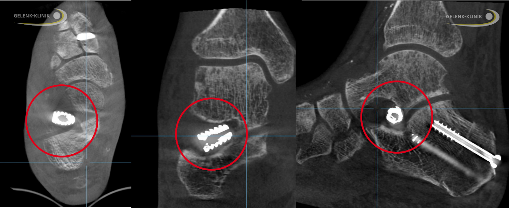

Arthrorise im Röntgenbild: Zu sehen ist der zwischen Fersenbein und Sprungbein eingesetzte Dübel (auch Spreiz-Prothese genannt). Durch dieses Implantat wird das Sprungbein aufgerichtet, was im Röntgenbild gut zu erkennen ist. © Dr. Thomas Schneider

Bei der subtalaren Arthrorise handelt es sich um den Überbegriff für verschiedene Verfahren, mit denen die krankhafte Kippung im unteren Sprunggelenk durch ein Implantat blockiert wird. Verwendet werden dazu ein Dübel, ein Bolzen oder eine Schraube (Stopp-Implantat oder Stopp-Schraube), die im Sinus tarsi zwischen Sprungbein und Fersenbein eingebracht werden. In der Folge wird die Lage des Sprungbeins korrigiert und das Fußlängsgewölbe wieder aufgerichtet.

Der Eingriff erfolgt minimalinvasiv über einen kleinen Hautschnitt an der Fußaußenseite. Das Implantat ist titan- oder kunststoffbasiert. Bei Erwachsenen wird es meist belassen, es sei denn, es treten Probleme auf. Dann kann der Fußchirurg es bei einer Revision wieder entfernen und auf ein anderes Behandlungsverfahren umschwenken.